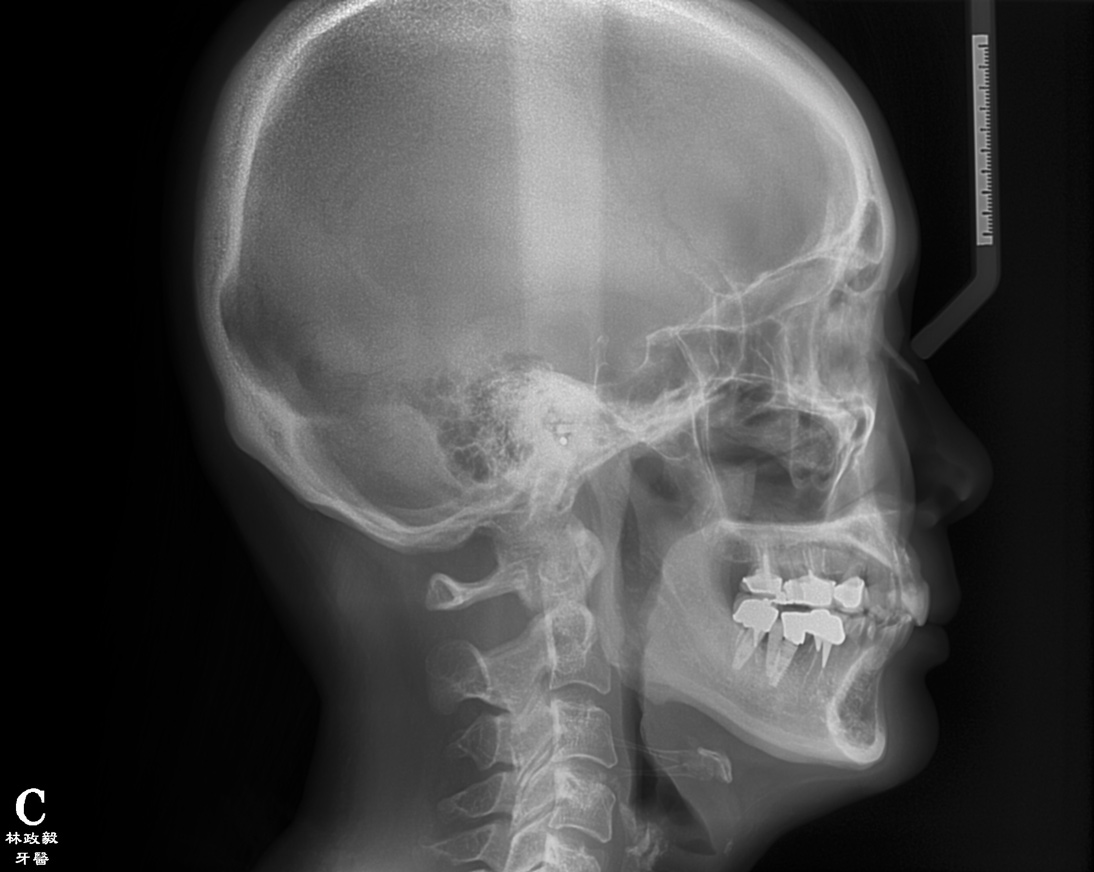

From radiographic examination, tooth No. 18 was found to have a poor prognosis due to furcation bone loss. The cephalometric x-ray showed a skeletal class II relationship, a reduced mandibular plane angle, flared upper incisors, a deep bite, and significant overjet (Figure 6). The panoramic radiograph confirmed many restorations and that No. 19 was a dental implant (Figure 7). There were no symptoms of temporomandibular joint disorder.

Fig 6. Cephalometric film before treatment.

Figure 6